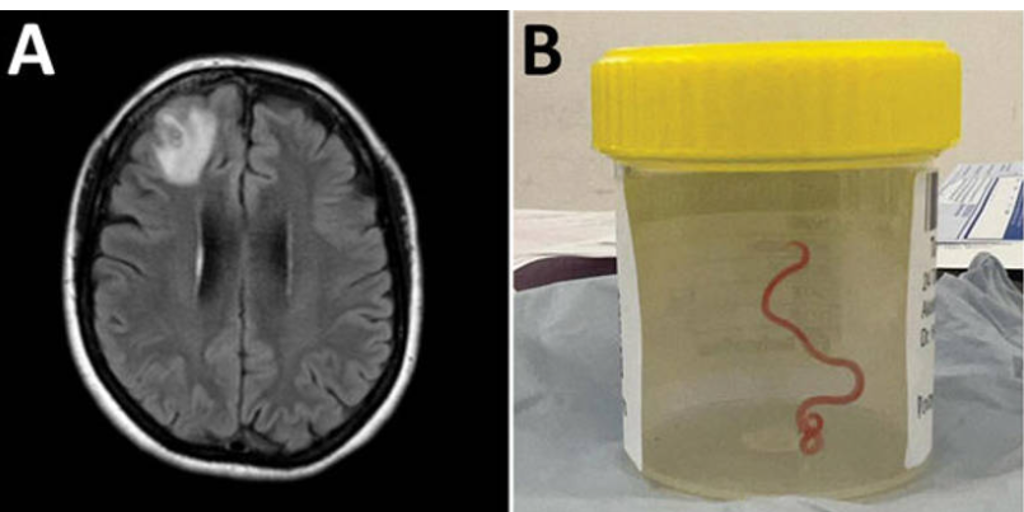

Para 2022, sus síntomas también incluían olvidos y depresión, lo que llevó a una derivación al hospital de Canberra. Una resonancia magnética de su cerebro reveló anomalías que requerían cirugía.

Sin embargo, la neurocirujana que abordó el caso, Hari Priya Bandi, encontró algo que parecía salido de una película de terror: un gusano parásito de 8 centímetros que aún estaba vivo y se retorcía. Finalmente, pudo extraerlo sin complicaciones.